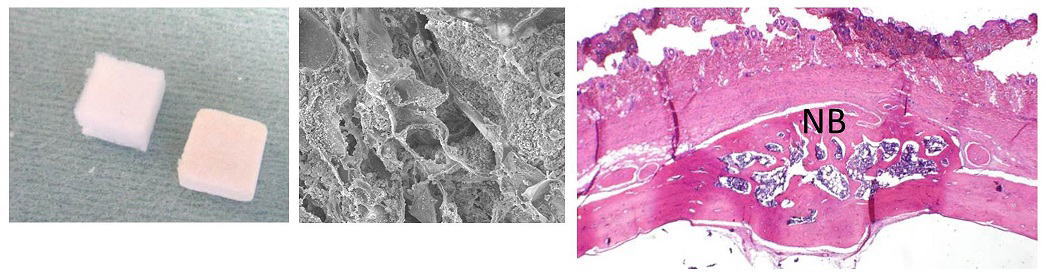

我々は、東京大学古月研究室との共同研究により、リン酸カルシウムを約100 nm 程度まで粉砕・微粒子化し、コラーゲン足場材料(スキャフォールド)に配合することで、材料の生体活性(バイオアクティビティ)を向上させることに成功しました。得られたリン酸カルシウムナノ微粒子は吸収性に優れ、タンパク質吸着やマクロファージの集積を促進することが確認されており、歯周組織再生を目的としたバイオマテリアルとして優れた特性を有すると考えられます。さらに、下図に示すように、β-トリカルシウムリン酸(β-TCP)ナノ微粒子を配合したコラーゲン足場材料は、ラット頭蓋骨モデルにおいて骨再生を誘導しました。本研究は2013年の Journal of Nanomaterialsに掲載されました。

A Ibara, H Miyaji, B Fugetsu, E Nishida, H Takita, S Tanaka, T Sugaya, M Kawanami. Osteoconductivity and biodegradability of collagen scaffold coated with nano-β-TCP and fibroblast growth factor 2. J Nanomater, 2013, 639502 (1-11), 2013.